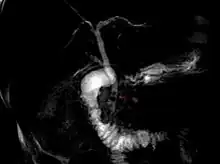

Magnetic resonance cholangiopancreatography (MRCP) image of two gallstones in the distal common bile duct | |

The diagnosis of choledocholithiasis is suggested when the liver function blood test shows an elevation in bilirubin and serum transaminases. Other indicators include raised indicators of ampulla of vater (pancreatic duct obstruction) such as lipases and amylases. In prolonged cases the international normalized ratio (INR) may change due to a decrease in vitamin K absorption. (It is the decreased bile flow which reduces fat breakdown and therefore absorption of fat soluble vitamins). The diagnosis is confirmed with either a magnetic resonance cholangiopancreatography (MRCP), an endoscopic retrograde cholangiopancreatography (ERCP), or an intraoperative cholangiogram. If the patient must have the gallbladder removed for gallstones, the surgeon may choose to proceed with the surgery, and obtain a cholangiogram during the surgery. If the cholangiogram shows a stone in the bile duct, the surgeon may attempt to treat the problem by flushing the stone into the intestine or retrieve the stone back through the cystic duct.